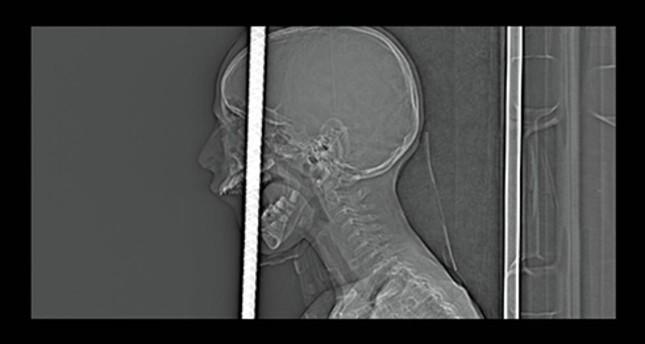

Seven Turkish doctors were able to successfully remove a piece of rebar that pierced through the mouth and impaled the skull of a 7-year-old boy who fell from his bike, after a five-hour surgery Tuesday night in the Black Sea city of Zonguldak.

Fırat Başaran was riding his bike in front of his house in Yeşil neighborhood Tuesday afternoon when he fell 5 meters onto an iron rod that entered his mouth, pierced his brain and broke through his skull.

Fire and medical teams cut the rebar to 1 meter in length and rushed Başaran to Zonguldak Atatürk State Hospital for emergency care. He was then brought to Bülent Ecevit University (BEU) Health Practice and Research Hospital for expert treatment.

Staff from the Disaster and Emergency Management Presidency (AFAD) also assisted in the surgery, cutting the rebar down to 3 centimeters.

After five hours, the medical team successfully removed the iron rod from Başaran's head. The 7-year-old remains in a life-threatening condition in the intensive care unit (ICU).